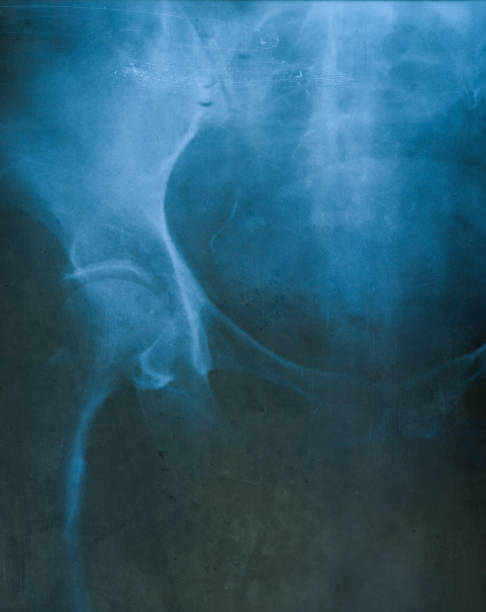

골반 통증 원인 5. 대퇴골두 무혈성 괴사

골반 통증 원인 다섯 번째는 대퇴골두 무혈성 괴사입니다. 이름은 어렵지만 대퇴 골두 무혈성 괴사의 경우 넓적다리 위쪽에서 대퇴 골두로 가게 하는 혈액의 흐름을 차단하기 때문에 뼈 조직이 죽으며 엉덩이 부위와 골반 통증을 유발하는 질병입니다. 따라서 괴사가 발생하더라도 초기에는 아무런 증상을 느낄 수 없다는 점이 특징이기 때문에 조금의 통증이라도 느껴지면 빠른 진료가 필요하며 심해지면 고관절의 손상으로 이어지게 되어 주의가 필요합니다.

골반 통증 원인 7. 퇴행성 고관절염

골반 통증 원인 일곱 번째는 퇴행성 고관절염입니다. 퇴행성 고관절염은 고관절 부위 연골이 마모되고 손상되는 증상을 말하는데 별다른 외상이 원인이 아니라 퇴행성 변화로 인하여 이러한 통증을 유발하게 됩니다. 이 증상으로 말미암아 관절운동 범위가 축소되는데 동시에 절뚝거리는 증상을 동반하며 골반 통증이 생깁니다.